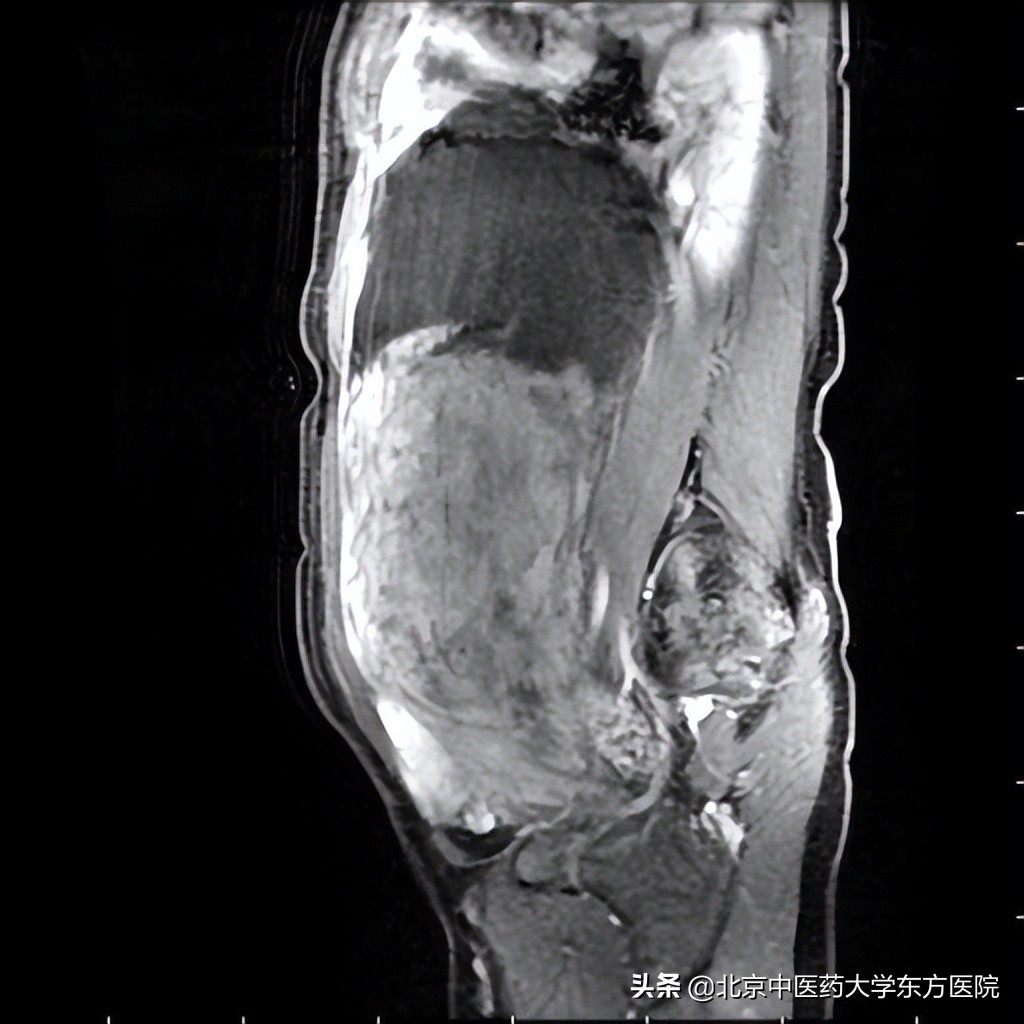

40多岁的李女士感觉最近发胖了,还偏偏只是肚子胖,而且还有继续长大的趋势,但四肢依然纤细,她以为是怀孕了,但查尿早早孕是阴性,也没有腹胀便秘、胸闷气短、恶心呕吐等任何不适症状,月经也很正常,难道是得了什么疑难杂症?李女士带着疑惑来到家附近的北京中医药大学东方医院检查,先是挂了外科,医生给她开了个腹部CT检查,CT提示盆腔内有巨大包快。这下可把李女士吓坏了,原本只是来医院做个体检,找到近期发胖的原因,没想到一查查出了一个像怀了足月孩子那么大的巨大肿物,不会是得癌症了吧?李女士寝食难安,在外科医生的建议下,来到妇科就诊,进行增强核磁检查,提示腹腔及盆腔巨大占位,子宫受压,边缘显示不清。不管肿物是良性还是恶性都需要尽快手术切除,于是妇科主任佟庆迅速安排患者入院。

由妇科主任佟庆主刀,术中发现肿物从子宫后壁长出,肿物巨大,占满了整个盆腹腔,想从腹腔内把肿物完整分离后取出极其困难。肿物里面有液体,主任提出把液体吸出来,缩小瘤体后再分离取出肿物。术中吸出1500ml液体,瘤体较前略有缩小,接下来想要完整取出肿物,还需要小心分离肿物后壁的广泛致密粘连,既不能损伤周围脏器,又要维持肿物的完整性,手术难度再次升级。4个小时后,在妇科主刀团队、麻醉科、普外科的共同努力下,终于完整取出肿物。经测量,肿物的直径足足有31cm,重约5kg。术中冰冻病理提示肿物为子宫肌瘤变性。如此巨大的子宫肌瘤实属罕见。术后妇科主管医生以理气养血,化瘀止血的中药配合耳穴、艾灸等中医内外治疗法,促进了李女士的术后恢复和排气,最终在病房医护的精心照顾下李女士恢复良好,如期出院。术后1个月复查时,李女士及家属对医院医护人员的帮助表达了深切的感激之情!